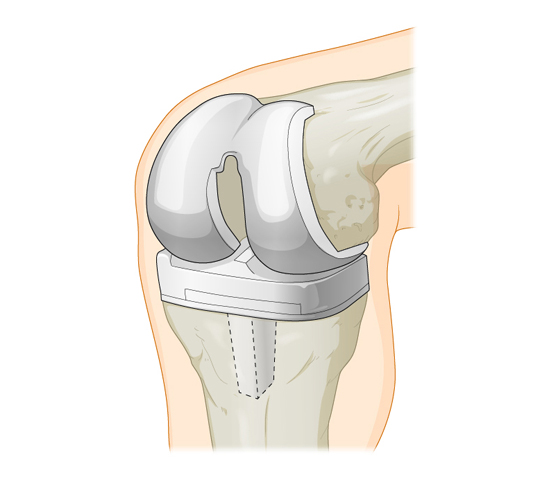

Фотографии и примеры протезирования коленного сустава